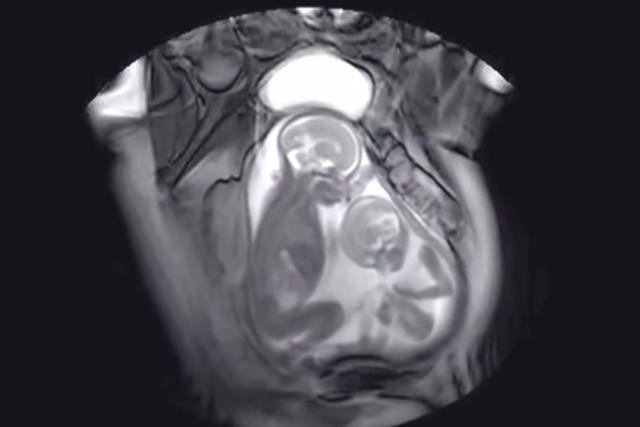

Naukowcy z berlińskiego Uniwersytetu Medycznego Charité postanowili kontynuował pracę swoich holenderskich kolegów. Owocem ich pracy jest pierwszy film z porodu od wewnątrz. Poród siłami i drogami natury odbył się w specjalnej komorze rezonansu magnetycznego. Celem badań było lepsze poznanie fizjologi ludzkiego ciała podczas porodu.

Około 15% porodów wymaga ukończenia poprzez zabieg cesarskiego cięcia. Obserwując fizjologię narodzin oraz mechanizm porodu w obrazie rezonansu, naukowcy mają nadzieję na lepsze poznanie przyczyn niepowodzeń porodów drogami natury.

Do przeprowadzenia badania skonstruowano otwarte urządzenie, ponieważ w klasycznej tubie aparatu nie zmieściłby się zespół prowadzący poród.

Na filmie doskonale widać skurcze macicy podczas akcji porodowej. Zaobserwować można jak ich siła wypycha dziecko, gdy skurcz mija malec cofa się w kanale rodnym kobiety. Warto podczas oglądania filmu zwrócić uwagę na trudną i męczącą drogę, którą pokonuje dziecko.